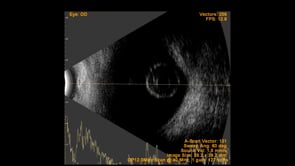

Left Eye B-scan ultrasound of a patient with old retinal detachment shows open funnel shaped hyperechoic membranous echoes, with high amplitude spikes on A-scan and a poor after-movement on dynamic B-scan, suggestive of retinal detachment. We can see a round echogenicity in sub-retinal location, with clear contents within, suggestive of a retinal cyst. This B-scan image is indicative of a long-standing chronic retinal detachment with secondary retinal cyst.

Photographer: Dr. Shraddha Raj Shrivastava

Condition/keywords: B scan ultrasound, chronic retinal detachment, OLD RD, open funnel RD, retinal cyst